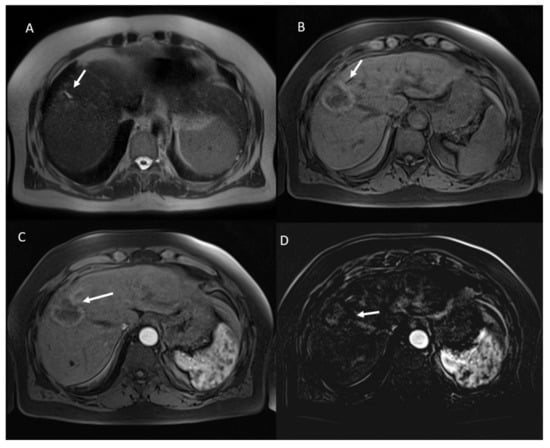

- 23 lesions were hyperintense in T2-W and hypointense in T1-W sequences (Figure 3).

- 98 showed iso-hypointense SI in T2-W and 15 iso-hyperintense SI in T2-W (Figure 6).

- 100 showed hyperintense SI in T1-W and 113 targetoid appearance.